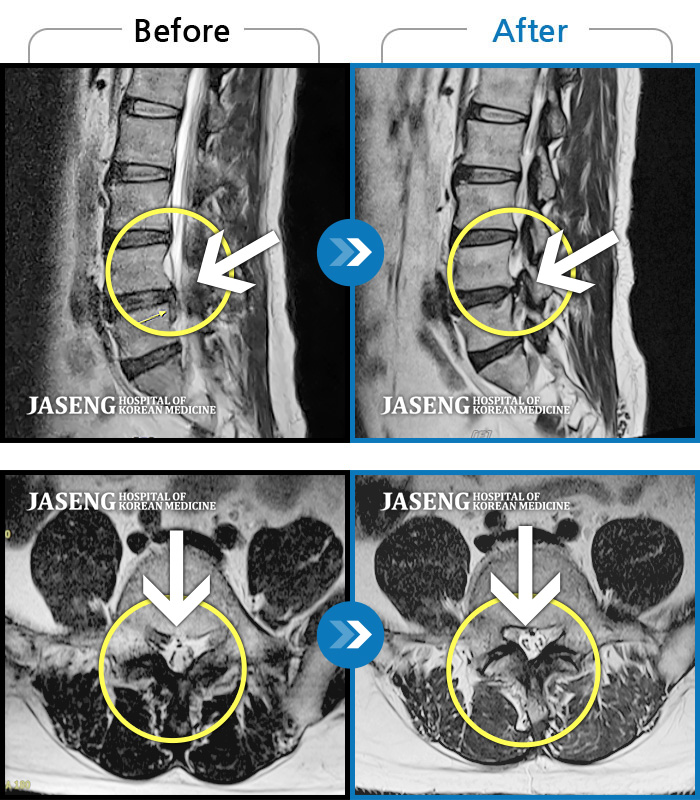

MRI 치료사례

허리 통증, 다리 근력 저하